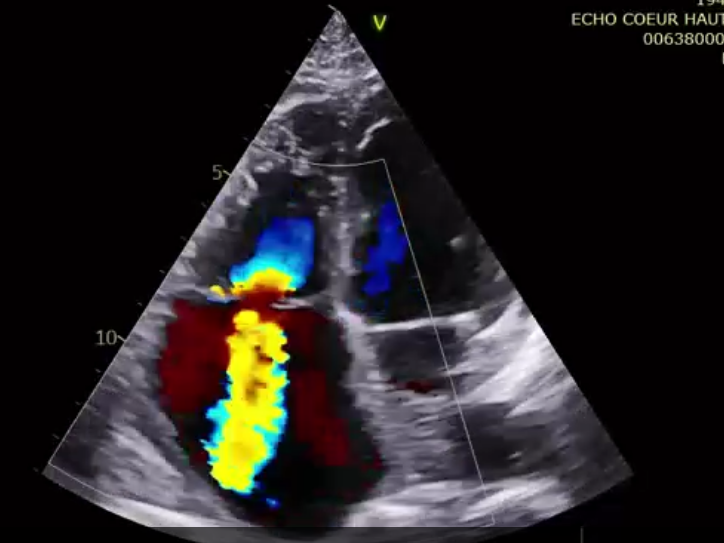

術(shù)后超聲提示微量瓣周漏